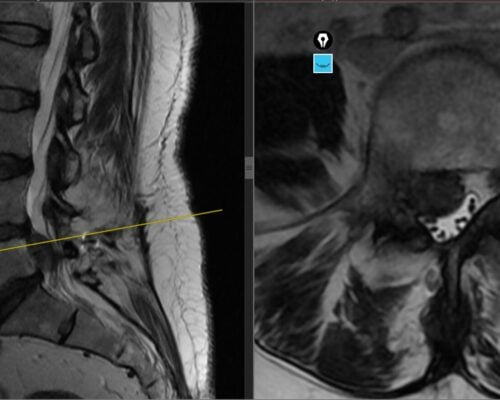

Studiu de caz: Spondiloză cervicală cu compresie medulară tratată prin decompresie ultra-laterală minim-invazivă – Recuperare neurologică rapidă

Spondiloza cervicală reprezintă una dintre cele mai frecvente cauze de afectare progresivă a măduvei spinării la pacienții peste 50 de ani. Problema majoră nu este lipsa tratamentului, ci întârzierea diagnosticului, deoarece simptomele inițiale sunt adesea subtile și atribuite procesului normal de îmbătrânire. Pacienții descriu frecvent dificultăți în activități fine, scăparea obiectelor din mână sau senzația […]